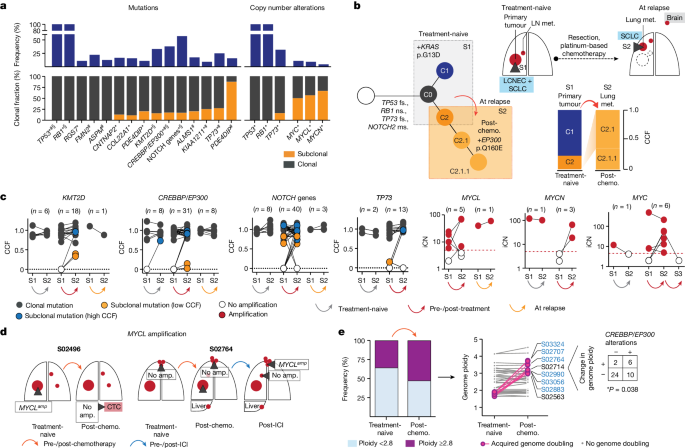

Clonality of central genome alterations

We next sought to identify those genomic alterations that segregate with treatment-associated clonal diversity in SCLC. We confirmed a key role of TP53 and RB1 , which were altered as part of the common ancestral clone in all patients (Fig. 4a , Extended Data Figs. 4a and 5a–c and Methods ). In agreement with previous studies 26 , tumours with a combined histology at the time of first diagnosis (S02500, S02814 and S02917) also harboured TP53 and RB1 alterations as part of the common ancestor ( Supplementary Appendix ) whereas oncogenic mutations, such as in KRAS , were no longer apparent in relapsing tumours with SCLC histology 19 , 27 (Fig. 4b ).

a , Gene alterations referring to significant mutations (*), hotspots (#) and damaging mutations (§), and copy number alterations. NOTCH genes include all alterations affecting NOTCH family members ( Methods and Extended Data Fig. 4 ). Corrected Q <0.05. b , Tumour phylogeny of patient S02814 with mixed SCLC/LCNEC histology harbouring KRAS p.G13D at first diagnosis, and SCLC histology and acquired EP300 p.Q160E at relapse. Additional mutations annotated as ms (missense), fs (frameshift) or ns (nonsense). c , Change in CCF of key gene mutations across distinct tumour samples in a patient (S1, S2, S3) acquired either at first diagnosis (treatment-naive), post-treatment or at relapse. Mutations are shown as either clonal (part of the common most recent ancestor, grey), subclonal with lower CCFs (yellow) or higher CCFs identified in distinct samples (blue). For amplifications, changes in integral copy number (iCN) are plotted for distinct patient-matched samples, indicating either no amplification (white) or focal amplifications (red) exceeding iCN > 5 (red dashed line). d , Scheme for patients with subclonal occurrence of focal MYCL amplifications annotated for sampled tumour sites (dark grey wedges). e , Genome ploidy observed in paired tumours from patients at first diagnosis (treatment-naive) and following chemotherapy (post-chemo., n = 42). Tumours with acquired genome doubling are highlighted (pink, right), and cases with CREBBP / EP300 alterations are indicated (blue). Fisher’s exact test, two-sided, * P < 0.05.

Our genome data confirmed a significant role of key genes previously identified in cohorts enriched for early-stage tumours 5 , 6 . We also applied different approaches to identify significantly mutated genes with various levels of stringency and found that the core set of mutated genes was shared between other models and ours ( Methods , Supplementary Tables 6 – 9 and Extended Data Figs. 4 and 6 ). Whereas the functional relevance of CREBBP / EP300 and TP73 was identified previously when analysing locally clustered hotspot and damaging mutations 5 , 6 , our present cohort enriched for metastatic SCLC showed higher mutation frequencies of these genes ( Q < 0.01; Methods and Extended Data Fig. 4b ). We also identified significant focal chromosomal losses of TP73 and recurrent mutations of position R273 and other conserved residues in TP73 , which are homologous to known hotspot mutations of TP53 (ref. 28 ) (Extended Data Figs. 4c,d and 6a,b ). Our data thus further emphasize the functional relevance of TP73 and CREBBP / EP300 in advanced-stage SCLC.

We performed a combined analysis of this cohort and previously published datasets 4 , 5 , 6 ( Methods ), which showed significant mutations in ephrin-type B receptor 1 ( EPHB1 ) and neuronal cell-adhesion gene CNTNAP2 (Supplementary Table 8 and Extended Data Figs. 4a,e and 6d,e ). Although the majority of these significantly mutated genes were frequently part of the common ancestor (Fig. 4a ), some exhibited signs of ongoing subclonal evolution including protein-damaging alterations, hotspot mutations and focal losses affecting CREBBP / EP300 , TP73 , KMT2D and NOTCH genes (Fig. 4c and Extended Data Fig. 5a–d ). Several of these alterations were enriched in the outgrowing tumour at relapse, thus further indicating a role in conferring acquired resistance to chemotherapy. To our surprise, significant high-level focal amplifications of all three MYC family genes ( MYC , MYCL1 and MYCN ) were frequently identified as subclonal events private to one tumour site sampled (56%, n = 9 of 16 cases), occurring either before ( n = 3) or after therapy ( n = 6), whereas patient-matched spatially or temporally distinct tumours lacked the amplification event (Fig. 4c,d and Extended Data Figs. 4c and 5e,f ). Thus, despite their undoubted role in SCLC 29 , 30 , 31 , 32 , MYC gene amplifications are often not part of the most recent common ancestor.

SCLC genomes are frequently polyploid, which is typically associated with inferior clinical outcome in cancer 33 , 34 . In our cohort, 36% of untreated tumours ( n = 15 of 42) exhibited with higher ploidy, which had no impact on clinical response to first-line therapy and clonal diversity throughout treatment (Extended Data Fig. 5g ). However, in these 42 pairs of tumours obtained before and after chemotherapy, tumours in eight patients exhibited events of acquired genome duplication at the time of recurrence. The majority of these tumours harboured either functionally relevant HAT domain mutations 6 or damaging alterations in CREBBP / EP300 , all of which were part of the common ancestor ( n = 6 of 8, * P < 0.05; Fig. 4e and Extended Data Figs. 5g and 6c ). Thus, acquired resistance in tumours bearing clonal CREBBP / EP300 alterations may be driven by genome duplication, which could potentiate the oncogenic functions of CREBBP / EP300 already present in the founder clone 33 , 34 .

We could not identify significant mutations that occurred exclusively in subclonal fractions across all patients, or those that may be related to specific mutational processes. Thus, overall, our observations provide further support for a central role of the founder clone, universally defined by mutations of TP53 and RB1 , in driving relapse. Furthermore, in several instances specific somatic alterations in genes implied in the biology of SCLC are enriched—but not exclusively—in recurring tumours and are therefore also likely to play a mechanistic role in the processes of drug sensitivity.